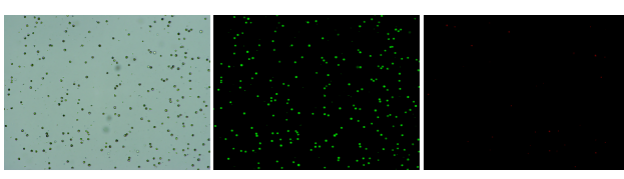

樣本設(shè)計:12例原發(fā)肝癌和6例早期復(fù)發(fā)肝癌患者的腫瘤組織和癌旁組織,進行全長單細胞轉(zhuǎn)錄組測序,并采用2個獨立的隊列(第1隊列,4例患者的配對原發(fā)腫瘤和復(fù)發(fā)腫瘤;第2隊列,47例患者的配對原發(fā)腫瘤和復(fù)發(fā)腫瘤)對相關(guān)結(jié)果進行驗證(見下圖)。

研究內(nèi)容:本文構(gòu)建了12例原發(fā)性肝細胞癌患者和6例早期復(fù)發(fā)肝細胞癌患者癌和癌旁的單細胞圖譜,發(fā)現(xiàn)與原發(fā)性肝癌微環(huán)境相比,復(fù)發(fā)性肝癌呈現(xiàn)獨特的免疫生態(tài)系統(tǒng),即DC比例增加,Tregs減少,T細胞增殖減少,CD8+T細胞豐度更高。通過整合TCR克隆和Monocle分析,研究者確定了CD8+T細胞的分化路徑。PT和RT樣本中CD8+T細胞表現(xiàn)出相同的分化軌跡,但表現(xiàn)出明顯不同的免疫和轉(zhuǎn)錄狀態(tài),與原發(fā)性肝癌樣本(PT)相比,早期復(fù)發(fā)性肝癌樣本(RT)中的CD8+T細胞耗竭信號的表達減少,表達免疫檢查點基因的細胞比例減少,組織駐留基因增加,而共刺激和耗竭分子減少。同時,研究者發(fā)現(xiàn)免疫檢查點基因CTLA4、HAVCR2和TIGIT在復(fù)發(fā)腫瘤的T細胞中表達降低,這表明針對這些標志物的檢查點阻斷方法可能對原發(fā)性肝癌有效,但對復(fù)發(fā)患者無效。綜上所述,治療原發(fā)性或復(fù)發(fā)性肝癌需要不同的治療方法。